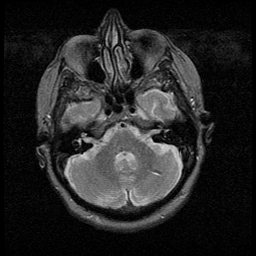

Huntington's Chorea, MR -- Slice #3

[Home][Help][Clinical] Slice 3